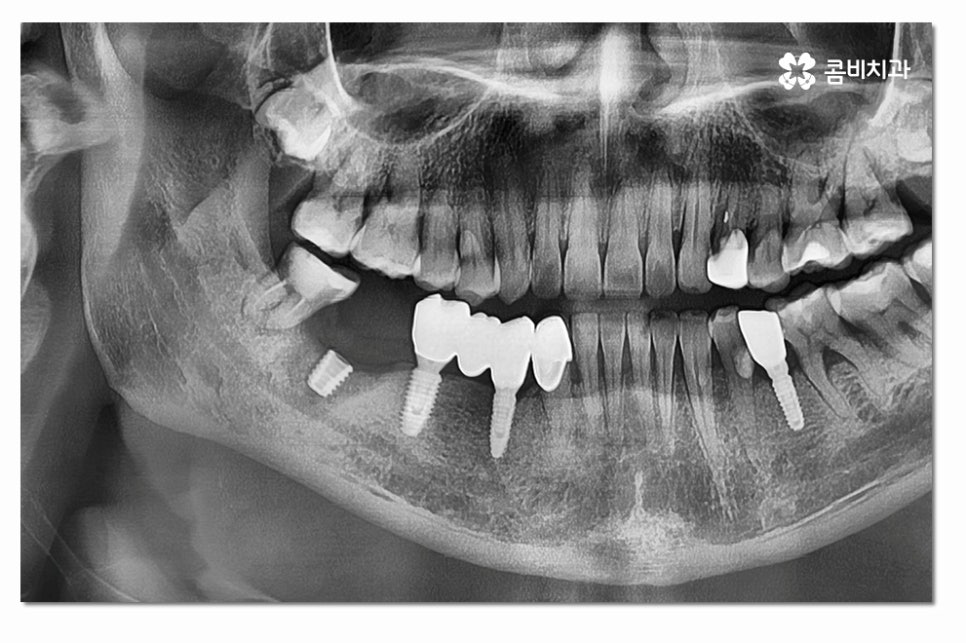

어금니임플란트의 경우 심미성보다는 기능성에 보다 집중된

치료가 이뤄지게 되는데 요즘은 3D CT 등을 통해

정확도 높은 진단이 이뤄지고 있지만 시술은 의사의 경험과

실력이 중요한 부분이기 때문에 어금니임플란트는

특히 저작기능을 수행하는 데 유리한 식립 각도와

위치 선정을 잘하는 것이 중요하다고 할 수 있어요.

자연치아와는 달리 어금니임플란트 시술 후에는 신경과 치주인대가

없기 때문에 관리에 소홀해지면 부작용이 발생할 수 있기 때문에

시술 후에는 평소 칫솔질과 함께 치실 또는 워터픽 사용을 꼼꼼하게 해야 하며

별다른 불편함이 없어도 정기적으로 치과에 방문하여 점검하는 것이 중요할 수 있어요.